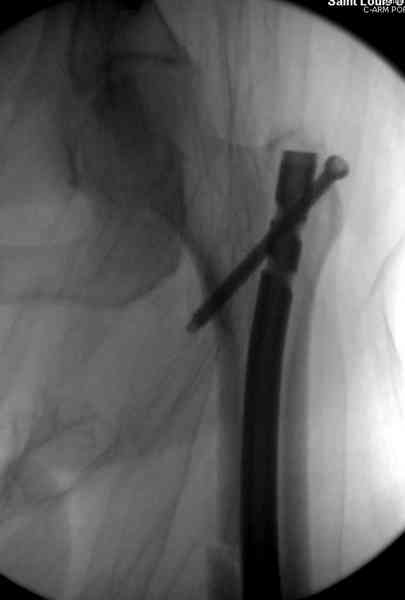

и проведены шурурпы через и спереди штифта без удаления.

Послеоперационные снимки